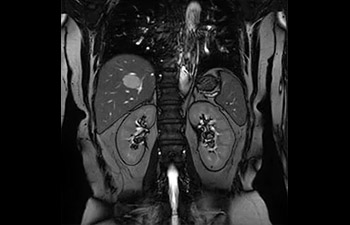

Tronco

Hemangioma hepático.

con Compressed SENSE